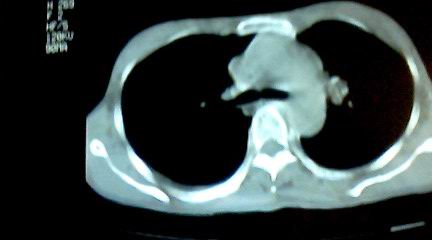

标题: CT25218:请教!胸部CT,胸8椎体骨质破坏,伴周围软组织肿。

患者,女41岁,肢体乏力。

两肺上叶继发性肺结核;胸椎结核并椎旁寒性脓肿形成。

胸椎结核并椎旁寒性脓肿形成。